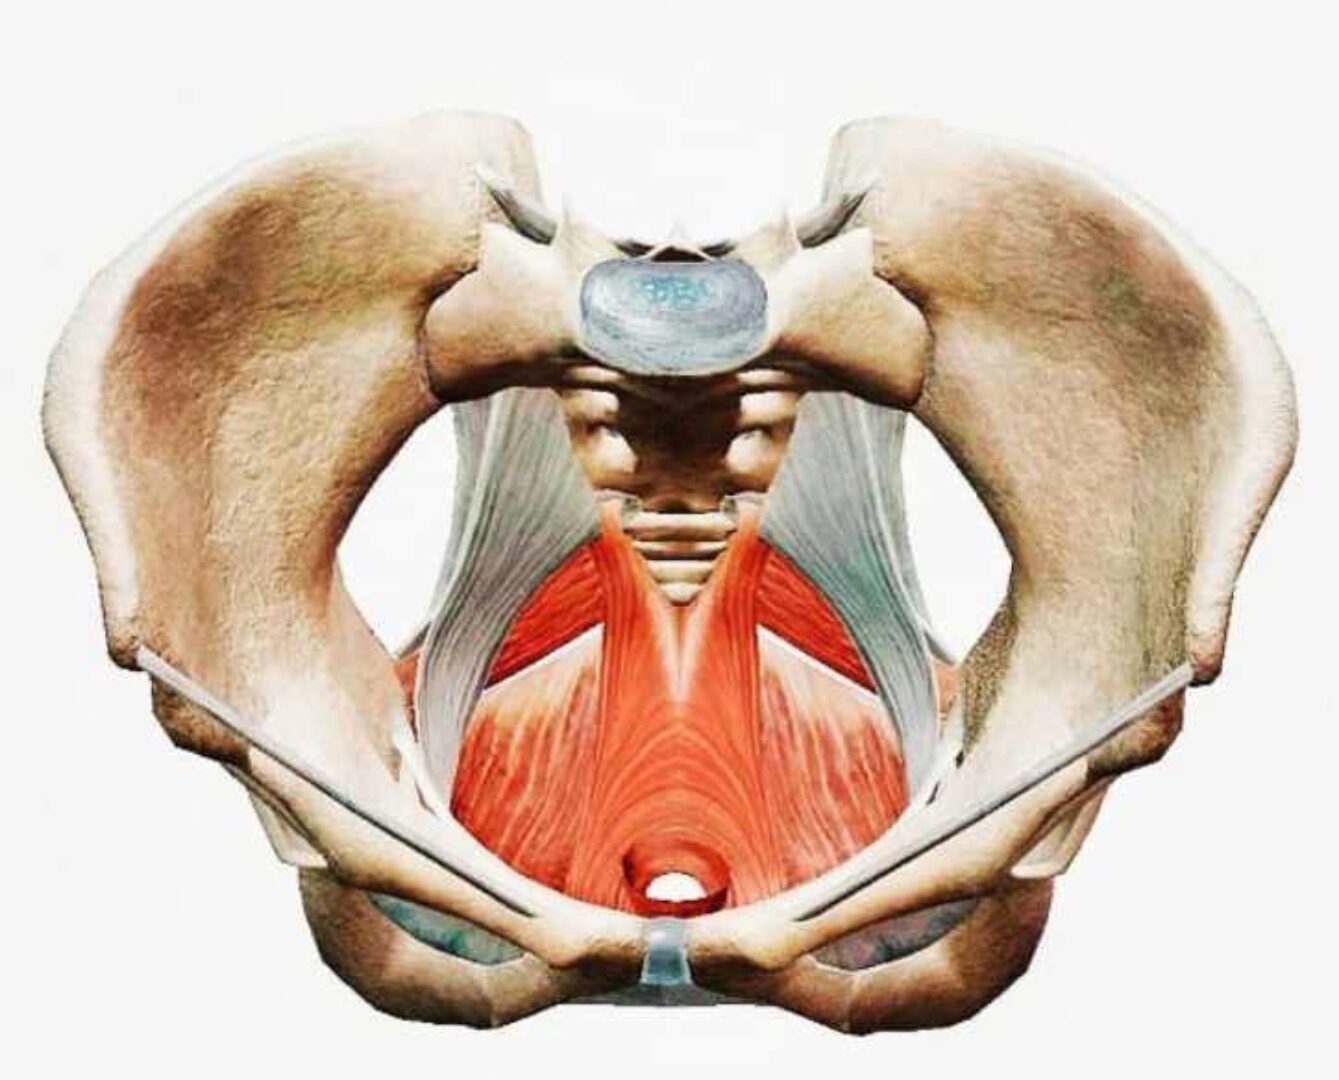

2. Восстановление функциональной связи мышц тазового дна, дыхательной диафрагмы и «глубокого мышечного блока».

3. Факторы риска, повышающие нагрузку на тазовый регион.

4. Алгоритмы восстановления мышц тазового дна при несостоятельности, после родов, при дисрегуляции, при гипертонусе.

5. Принципы построения индивидуальных и групповых программ по реабилитации тазового дна.

Мышцы тазового дна и Кор. Алена Кабанец КАЖДАЯ ТРЕТЬЯ ЖЕНЩИНА, независимо от возраста, имеет ту или иную дисфункцию мышц тазового дна! ⠀ Проявляется это как: - Стрессовое недержание во время кашля, смеха, прыжков, бега - Частое хождение в туалет днём и особенно ночью - Кишечная дисфункция

Самый частый запрос, с которым ко мне обращаются женщины... это недержание мочи после родов. И это неудивительно, ведь с такой проблемой по статистике сталкивается каждая 4 женщина уже после первых родов. Это связано в первую очередь с потерей здорового тонуса мышц тазового дна - женского